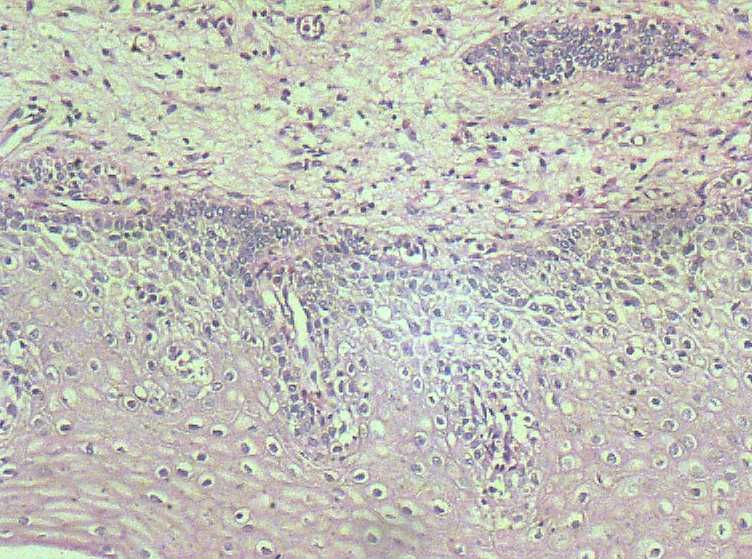

33岁 宫颈刮片看上去很像腺上皮病变,报了AGC 建议活检。 活检取自宫颈,图片如下:请帮忙看下,谢谢!

鳞状上皮增厚,乳头状增生,并见挖空样细胞。提示HPV感染。

有不典型增生, 不知道大家有没有看到。  如果有不典型和上面的图像可或直接报 :尖锐湿疣伴不典型增生。

今天把刮片的图片上了,只是拍的图片效果不好。这张刮片的表层鳞状上皮 很好  没有看到不明显的不典型,也没有看到明显的挖空细胞  。那些一堆堆的细胞  不管从形态 和排列上我 觉得都像 腺上皮的  不过有一点不太像就是没有看到明显的核仁 。这张片的组织学  我报了 符合(宫颈)尖锐湿疣伴不典型增生 。建议HPV检测。不知妥否?请大家给予指点